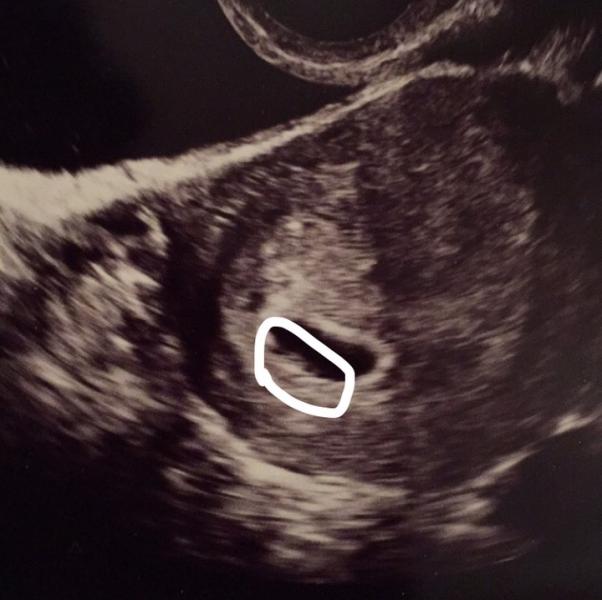

She said this shadow at the bottom of the gestational sac is the yolk sac. I don't see it? My friend says she sees a tiny little circle but I don't. Idk if the ultrasound tech just sucked cause it was a woman's center or if the baby isn't there. I can't stop worrying!!! 😖 and why does it look like my uterus is divided down the middle by a line?

@mimiz, @txkitten83 @polkadotcutie I see something but it's not a circle yolk sac which is what bugs me. It's just a tiny blurry area.

I see it. It's just kinda early. I didnt see mine fully until 9 weeks.